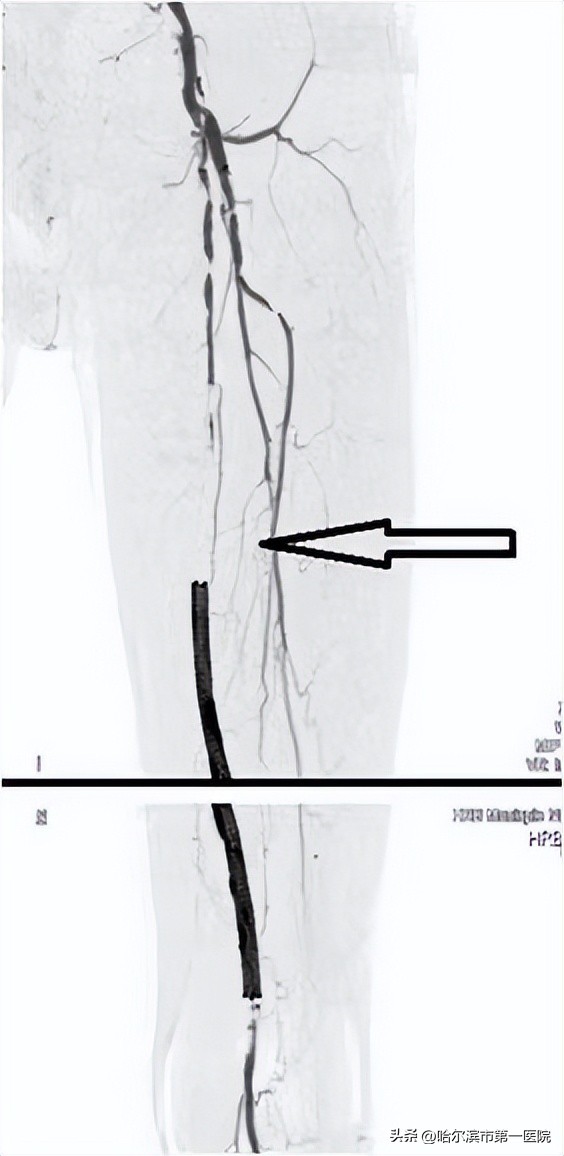

医生为王大爷进行了详细的问诊和查体。结合患者以往的症状和做过动脉支架的手术史,首选考虑患者是左下肢动脉支架内血栓形成。通过下肢动脉CTA结果证实了判断。以往处理支架内血栓需要开刀手术,切开取栓或者选择支架内再次支架,往往导致术后并发症,严重的病人可能出现肢体坏死截肢,甚至危及生命。经过与家属的充分沟通,决定采取目前先进的动脉机械吸栓(Rotarex)技术帮助老人解决目前的难题。不仅可以让王大爷避免麻醉的风险,也让术后的皮肤无创降低感染几率。

术中,在造影明确病变程度和位置后,周伟忠主任带领瞿鹏副主任医师、刘焱喆主治医师团队通过Rotarex导管头端的微小高速旋转装置将血栓切碎,继而通过抽吸导管运出体外。王大爷的左下肢做完手术后,皮温就明显变暖了,左下肢疼痛、麻木症状也得到了缓解。经过康复治疗,王大爷恢复良好,现已出院。